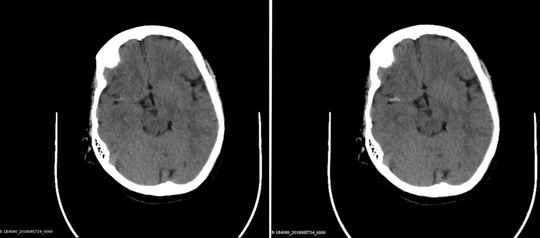

Abb. 1: Schädel-CT, links originale Schicht, rechts dieselbe Schicht, auf der der KI-Assistent den Thrombus erkannt und richtig umrandet hat. Diese Segmentierung erfolgt automatisch über mehrere aneinander grenzende Schichten, und zu jeder werden Kenngrößen zu Größe und Grauwertverteilung ermittelt

Der KI-Notfalldiagnostik-Assistent wird zunächst in drei Anwendungsbereichen trainiert: Schlaganfälle, Knochenverletzungen und Brustkorbuntersuchungen. Auf allen drei Gebieten geht es hauptsächlich darum, Probleme frühzeitig zu erkennen, die einer möglichst schnellen Behandlung bedürfen, zum Beispiel die richtige Platzierung von Kathetern, die der KI-Assistent anhand von Röntgenbildern überprüfen kann. Wenn in der Notaufnahme der Verdacht auf Schlaganfall besteht, soll das System anhand des Bildes automatisch erkennen, ob ein verschlossenes Blutgefäß oder eine Hirnblutung die Ursache ist – die dann jeweils nötige Therapie ist in den beiden Fällen grundlegend unterschiedlich – und, wenn ein Thrombus vorliegt, diesen markieren (Abb. 1). Bei der Untersuchung von Knochenbrüchen nach Unfällen kann die Bildanalyse erkennen, ob überhaupt ein akuter neuer Bruch vorliegt und auch, ob der frische Bruch etwa instabil ist (Abb. 2), so dass die Behandlung potenziell mit besonderer Vorsicht durchgeführt werden muss. Ärztinnen und Ärzte erhalten so eine schnelle fundierte Entscheidungsgrundlage für Notfallbehandlungen. Potenzielle Anwendungsgebiete darüber hinaus sind vielfältig. Vor allem kleinere Kliniken, denen es an entsprechender spezialisierter radiologischer Expertise fehlt, können von der KI-Anwendung profitieren. Eventuell kann sie sogar zu Trainingszwecken eingesetzt werden – nachdem die KI auf der Grundlage von Trainingsdaten gelernt hat, entsprechende Auffälligkeiten zu erkennen und von Experten freigegeben wurde, könnte die KI schließlich bei der Schulung von externem medizinischem Personal unterstützen.